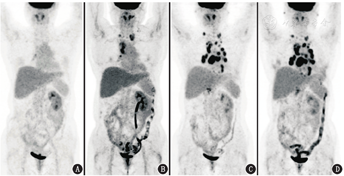

患者女,55岁,右输尿管癌术1年余,多疗程放化疗后,发现多发淋巴结肿大3个月。患者于2019年5月因右侧输尿管可疑恶性占位行"腹腔镜右侧半尿路切除术"(右肾+右输尿管全长+右输尿管开口周围部分膀胱切除),术后病理提示:肾盂输尿管高级别浸润性尿路上皮癌,侵及输尿管肌层,淋巴结转移癌(肾门1/1),手术病理分期pT2N1Mx(Ⅳ期)。术后1个月行18F-脱氧葡萄糖(fluorodeoxyglucose, FDG)PET/CT显像,未见肿瘤残留或转移(图1A)。后行3个疗程辅助化疗(吉西他滨+顺铂)及多次放疗(放疗野包括右侧肾窝及输尿管走行区、膀胱三角区、下腔静脉及右腹主动脉旁淋巴引流区),至2019年12月结束。2020年10月,患者自行触及双侧锁骨上区包块,2021年1月复查18F-FDG PET/CT新见双侧锁骨上/下、右肺门及纵隔多发代谢增高淋巴结,最大者位于纵隔4R区,大小约2.2 cm×1.7 cm,最大标准摄取值(maximum standardized uptake value, SUVmax)为7.4;腹盆部未见明显异常(图1B)。输尿管淋巴引流丰富,输尿管尿路上皮癌病程早期即易发生淋巴转移,通常先转移至区域淋巴结,与原发灶所在输尿管节段相关,而晚期疾病可转移至任意组淋巴结[1],加上腹盆腔淋巴引流区都经过了放疗,所以此次有可能直接出现颈胸部淋巴结的跳跃性转移。患者自2021年1月起,予度伐利尤单克隆抗体(简称单抗),其为程序性细胞死亡蛋白配体1(programmed death-ligand 1, PD-L1)阻断剂,属于免疫检查点抑制剂(immune checkpoint inhibitors, ICIs)治疗。4个疗程抗PD-L1治疗后于2021年4月复查18F-FDG PET/CT,相较于治疗前,新见纵隔、双肺门及上腹部多发代谢增高的肿大淋巴结(图1C)。患者之后继续接受6个疗程抗PD-L1治疗,2021年6月复查18F-FDG PET/CT,可见原颈胸部淋巴结数量、大小、代谢活性大多变化不明显(图1D)。

肿瘤治疗后的疗效可以用病灶大小、代谢活性变化来评估,可参照实体瘤疗效评价标准(response evaluation criteria in solid tumors, RECIST)[2]、实体瘤疗效PET评价标准(PET response criteria in solid tumors, PERCIST)[3]。在免疫治疗时代,有时肿瘤的疗效评价会变得复杂。ICIs是通过阻断免疫检查点通路,重新激活T细胞介导的抗肿瘤免疫,逆转免疫逃逸现象,从而促进肿瘤细胞死亡。在免疫治疗过程中,由于免疫细胞浸润、细胞内或血管源性水肿、炎性反应以及肿瘤内出血等原因,可能出现假进展效应,表现为肿瘤体积增大、代谢增高,甚至出现新发"病灶",但这并不是肿瘤细胞增多造成的[4]。ICIs治疗后的假进展平均发生时间在开始治疗后12周左右,其在应用抗细胞毒性T淋巴细胞相关蛋白4(cytotoxic T lymphocyte-associated antigen-4, CTLA-4)单抗治疗的黑色素瘤患者中发生概率约10%,在抗程序性细胞死亡蛋白1(programmed death-1, PD-1)或PD-L1治疗的其他实体瘤中发生概率不超过5%[5]。若临床怀疑假进展,建议4~8周后复查影像学检查确认。另一种ICIs治疗中的特殊效应是超进展,是指治疗后异常的肿瘤生长增速,治疗后第1次评估时(<2个月)肿瘤负荷增长>50%,且治疗后生长速率>2倍治疗前生长速率。超进展发生率在不同肿瘤中相差较大,通常认为实体瘤抗PD-1或PD-L1治疗后超进展发生率约10%[6]。超进展患者预后极差,怀疑发生超进展后需立即停用ICIs治疗并更换方案。

本例患者在开始抗PD-L1治疗后迅速出现了淋巴结病变明显增多、增大;继续维持治疗,淋巴结的病变又趋于稳定,变化不明显。如果考虑抗PD-L1治疗后新出现的淋巴结病变都是转移,是肿瘤的超进展,那么后续治疗过程中的变化并不符合肿瘤超进展的表现。仔细观察开始抗PD-L1治疗后出现的淋巴结病变,大多分布在肺门、气管周围,双侧分布较对称,淋巴结密度较均匀,没有明显的坏死、融合,这种PET/CT上的表现很符合结节病的代谢、形态、分布特征(图2)。